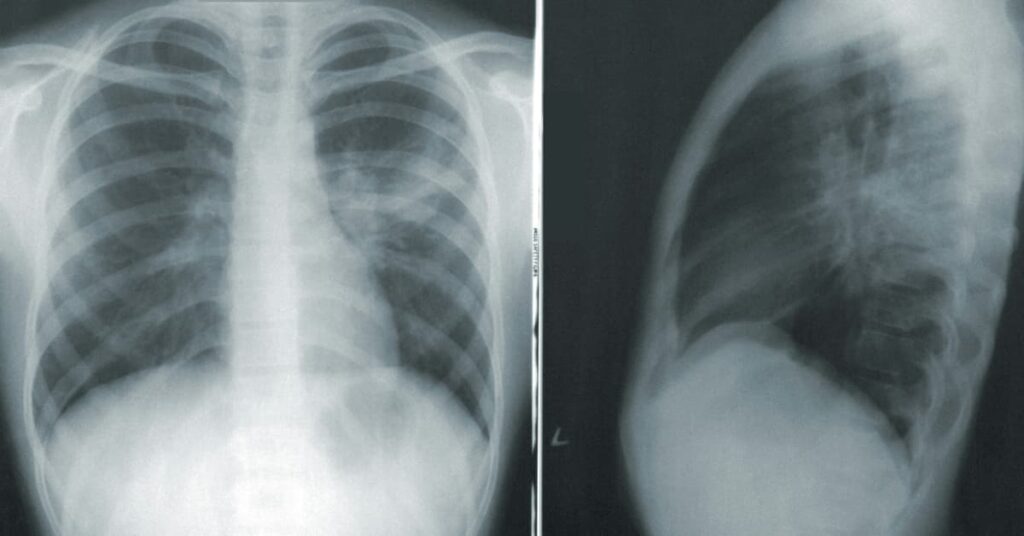

III. Based on Affected Lung Area (Radiological Pattern)

1. Lobar Pneumonia: Affects a large, continuous section (lobe) of one or both lungs.

2. Bronchopneumonia: Affects patches throughout the lungs, often involving the bronchi and bronchioles.

3. Interstitial Pneumonia: Affects the interstitial spaces between alveoli, often seen in viral and atypical bacterial pneumonias.

• Purpose: Continuous assessment of vital signs (temperature, respiratory rate, blood pressure (BP), heart rate, oxygen saturation) & clinical status to detect worsening or complications.

• Guidance: Regular checks by healthcare providers are crucial, with appropriate diagnostic tests (e.g., chest X-rays, blood tests) as needed.